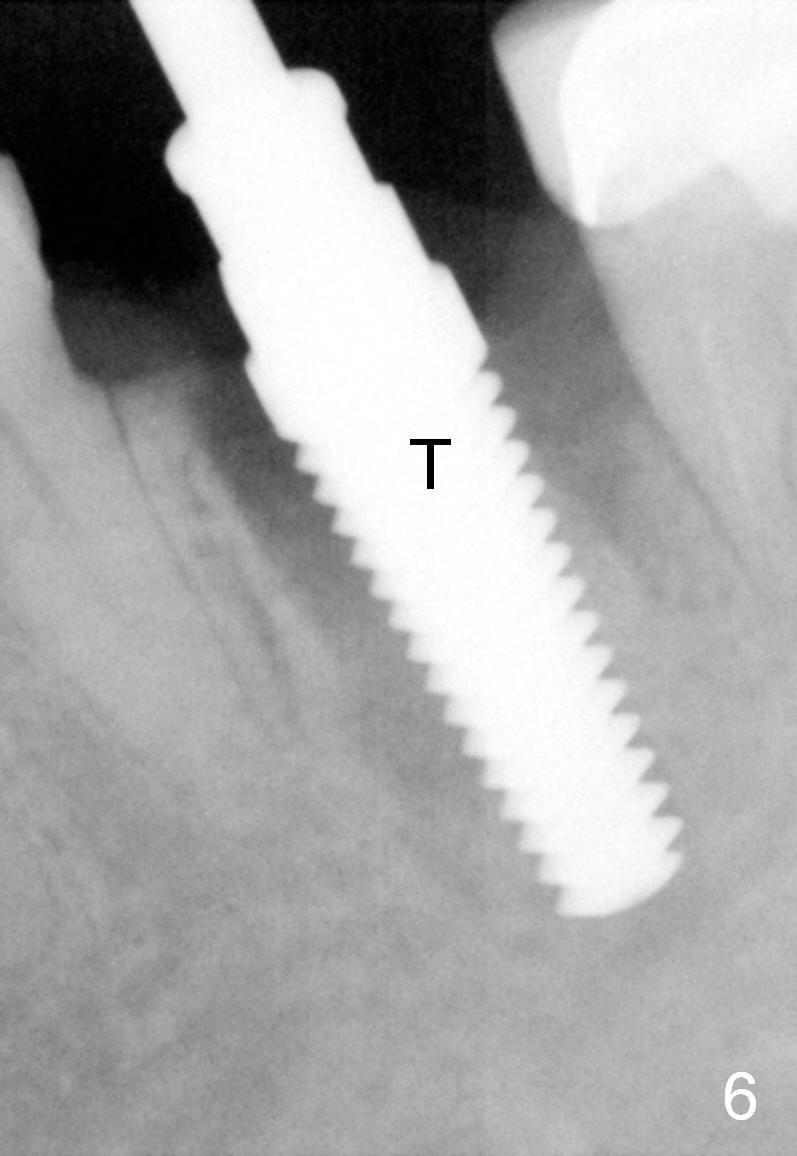

A 47-year-old lady lives out of town and presents to clinic with chief complaint "lower left back tooth easily bleeding with food impaction". Dental history and examination reveals failure of endo retreat of the tooth #19 (Fig.1), buccal gingival swelling (S), open access (A) and furcal and mesial periapical radiolucency (Fig.2 *). She is pleased to know availability of immediate implant and immediate provisional and accepts and receives the treatment at the same visit. The immediate implant (tissue-level) is designed to be as large as 7 mm and as long as 17 mm (Fig.3). To reduce paresthesia (yellow dashed line: the possible upper border of the Inferior Alveolar Canal)), a shorter implant (14 mm long in red line) is preferred. The tooth is extracted with sectioning. Granulation tissue is removed from the furca. The buccal plate appears to be intact. The septum is flat (Fig.4,10a S). Osteotomy starts in the middle of the septum with a 1.2 mm drill (Fig.10b red circle). As osteotomy increases in diameter (Fig.5 O), the apical end appears to be deviated mesiobuccally (Fig.10c large red circle). When a 6x17 mm tapered tap is being placed 14 mm deep (Fig.6 T), vibration of the buccal plate is seemingly felt at the apex (Fig.10d green circle). Further osteotomy may perforate the buccal plate. A 6x14 mm tissue-level implant is placed with >60 Ncm of insertion torque (Fig.7,8 I), followed by a 5x3 mm abutment (A) and bone graft (* in the remaining socket gap). An immediate provisional is cemented without occlusal contact (Fig.9 P).